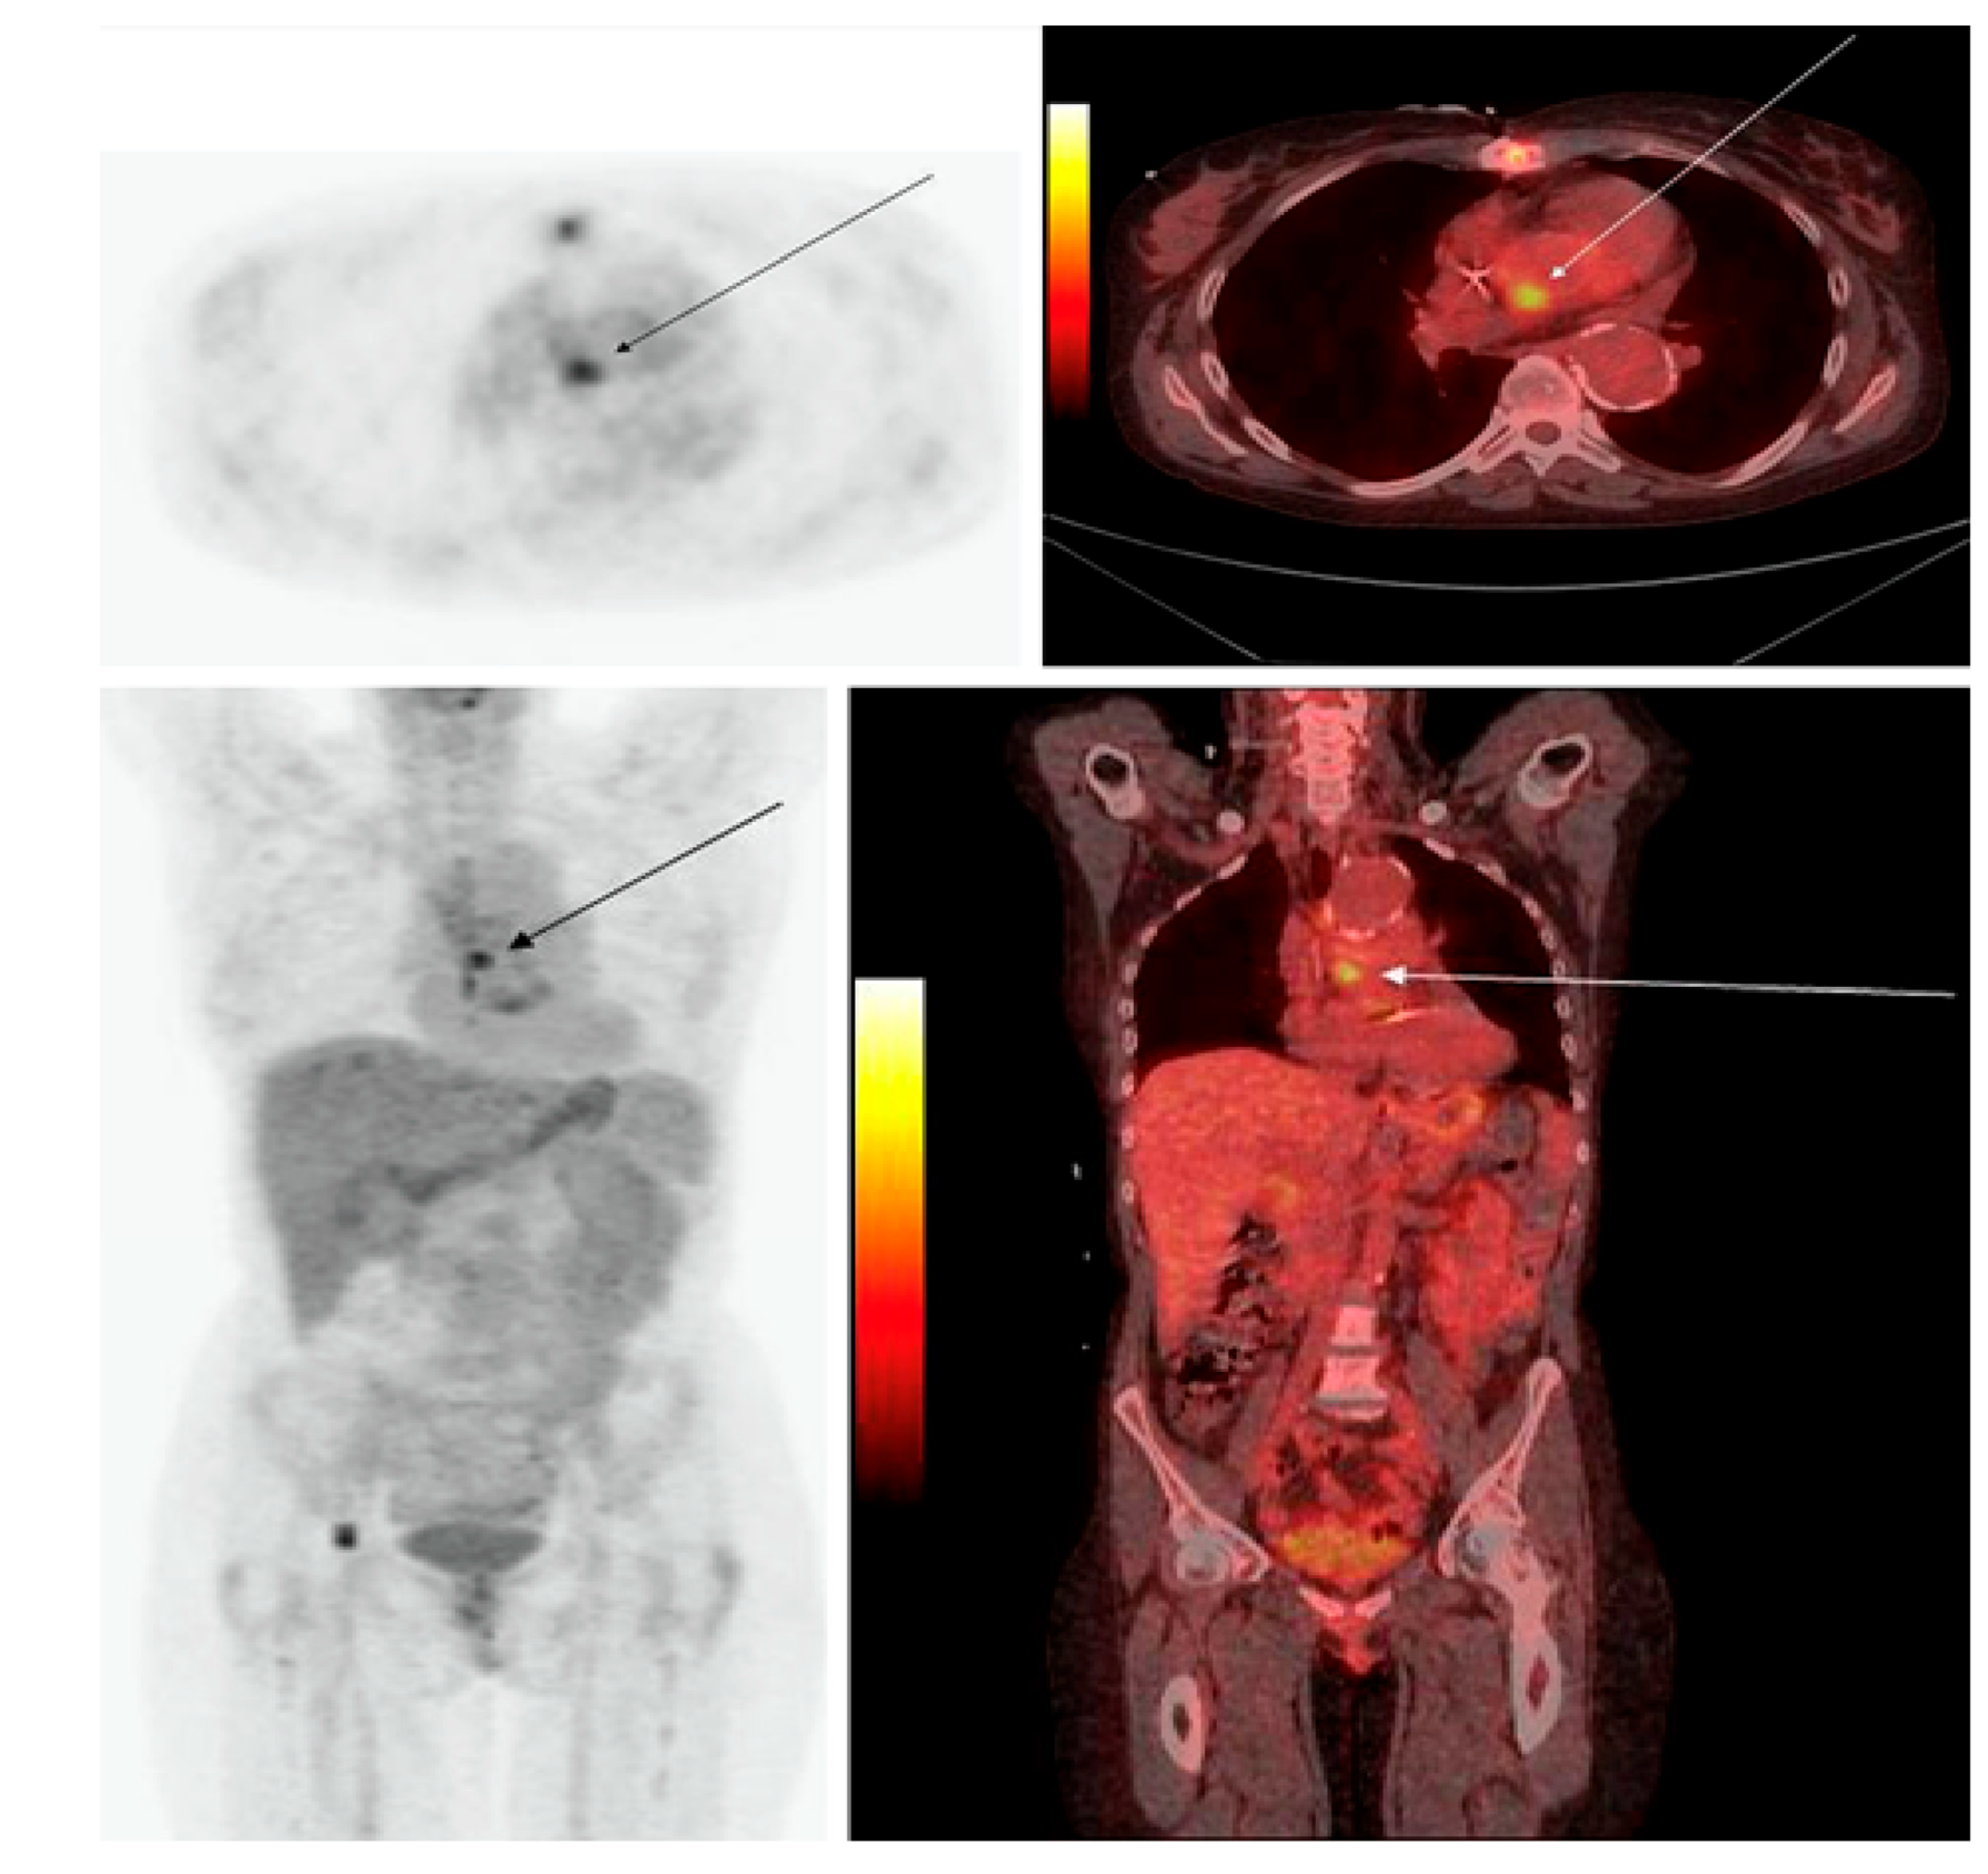

With the introduction of combined PET/computed tomography (CT) in 2001, PET/CT has become one of the most widely used imaging techniques for diagnosing infectious and inflammatory disorders [4]. However, [18F]FDG, as the molecular imaging test of choice for many inflammatory and infectious indications (including sarcoidosis, fever of unknown origin, and musculoskeletal infection), was only recently approved by the Centers for Medicare and Medicaid Services (CMS) in the United States [9]. All along, there has been a growing interest in exploring the usefulness of [18F]FDG-PET/CT in many infectious and inflammatory disorders beyond its original research trials [10]. The clinical use of PET imaging is being widely studied for chronic osteomyelitis, complicated lower-limb prostheses, complicated diabetic foot, fever of unknown origin (Figure 2), acquired immunodeficiency syndrome (AIDS), vascular graft infection, and fistula, among various other indications [10].

Figure 2. [18F]FDG-PET imaging in fever of unknown origin (FUO). A 44-year-old man after heart transplant presented with fever of unknown origin and inconclusive radiologic studies, including CT. Coronal PET images demonstrate a focus of increased [18F]FDG activity in the aortopulmonary window that represents the source of infection. The patient completely recovered following drainage of the infected site in the mediastinum (with permission from [10]).